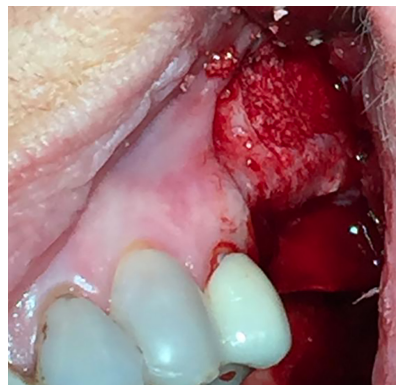

El abordaje quirúrgico fue realizado mediante una incisión lineal crestal y dos descargas verticales, mesial y distal, procediendo al despegamiento mucoperióstico para la obtención de un campo quirúrgico adecuado. Se realizó el diseño de una ventana lateral con piezoeléctrico (VarioSurgery®) (Figura 4), despegándose a continuación la membrana sinusal sin perforación alguna (Figura 5). A continuación, se procedió al relleno mediante un compuesto de fosfato de calcio-potasio-sodio bioactivo (Osseolive®) (Figura 6), acompañado de la colocación de una membrana de ácido poliláctico (EPI-Guide®) (Figuras 7 y 8), finalizando la intervención con la reposición del colgajo mucoperióstico y sutura con poliamida de 4/0 (Supramid®) (Figura 9).